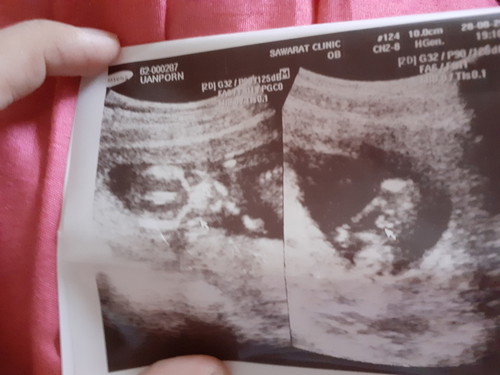

ญ หรือ ช คะ

ดูไม่ออกคะ หญิงหรือชายคะแม่ๆ?

เดานุคะชาย